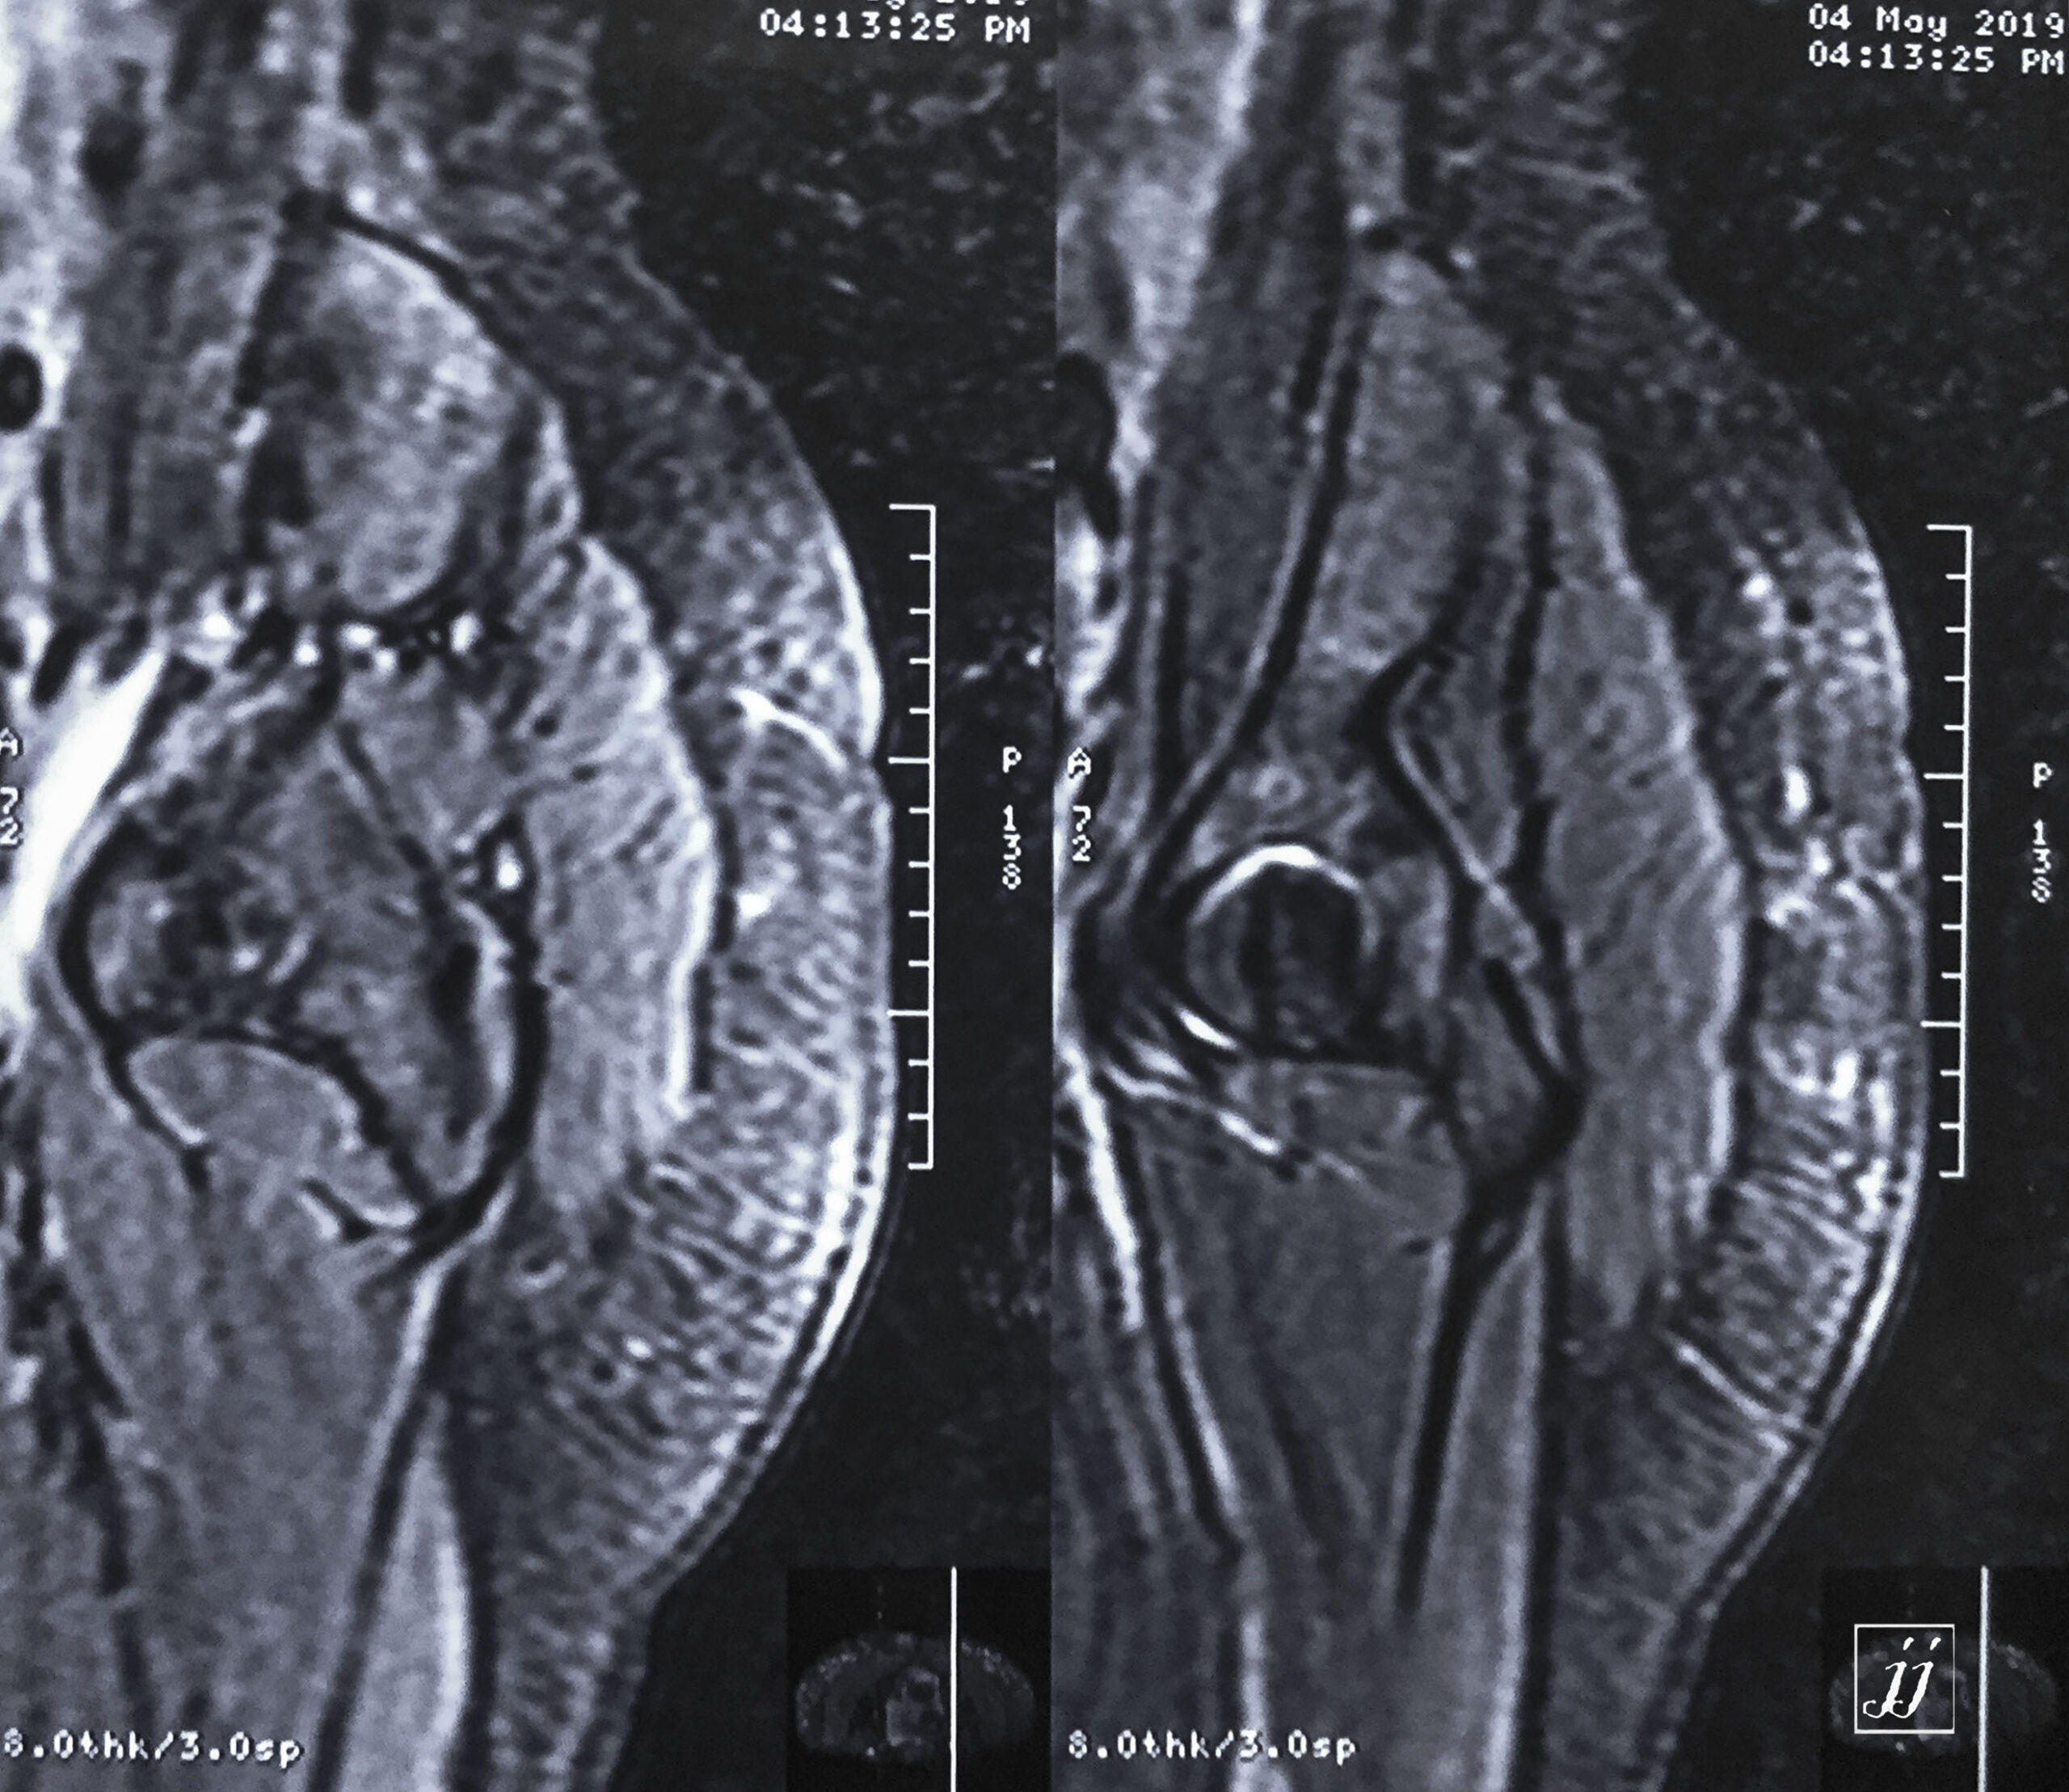

MSK- large intrapelvic mass (1)